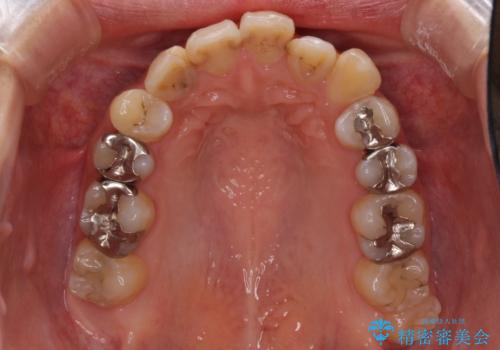

後戻りを治したい 骨格的なズレの大きい方のインビザライン矯正

- 中学生の時に矯正治療をしたものの、後戻りを気にして来院された患者様です。

骨格的に下顎が右側に変位しているため、左右の咬み合わせを理想的なものに改善することはできませんが、インビザラインにて歯列を整えることとしました。

骨格的なズレによる左右差は改善できませんでしたが、上下の正中を極力合わせるようにすることができました。